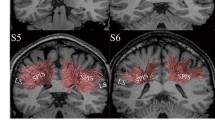

Mammalian cerebral cortices are characterized by elaborate convolutions. Radial convolutions exhibit homology across primate species and generally are easily identified in individuals of the same species. In contrast, circumferential convolutions vary across species as well as individuals of the same species. However, systematic study of circumferential convolution patterns is lacking. To address this issue, we utilized structural MRI (sMRI) and diffusion MRI (dMRI) data from primate brains. We quantified cortical thickness and circumferential convolutions on gyral banks in relation to axonal pathways and density along the gray matter/white matter boundaries. Based on these observations, we performed a series of computational simulations. Results demonstrated that the interplay of heterogeneous cortex growth and mechanical forces along axons plays a vital role in the regulation of circumferential convolutions. In contrast, gyral geometry controls the complexity of circumferential convolutions. These findings offer insight into the mystery of circumferential convolutions in primate brains.